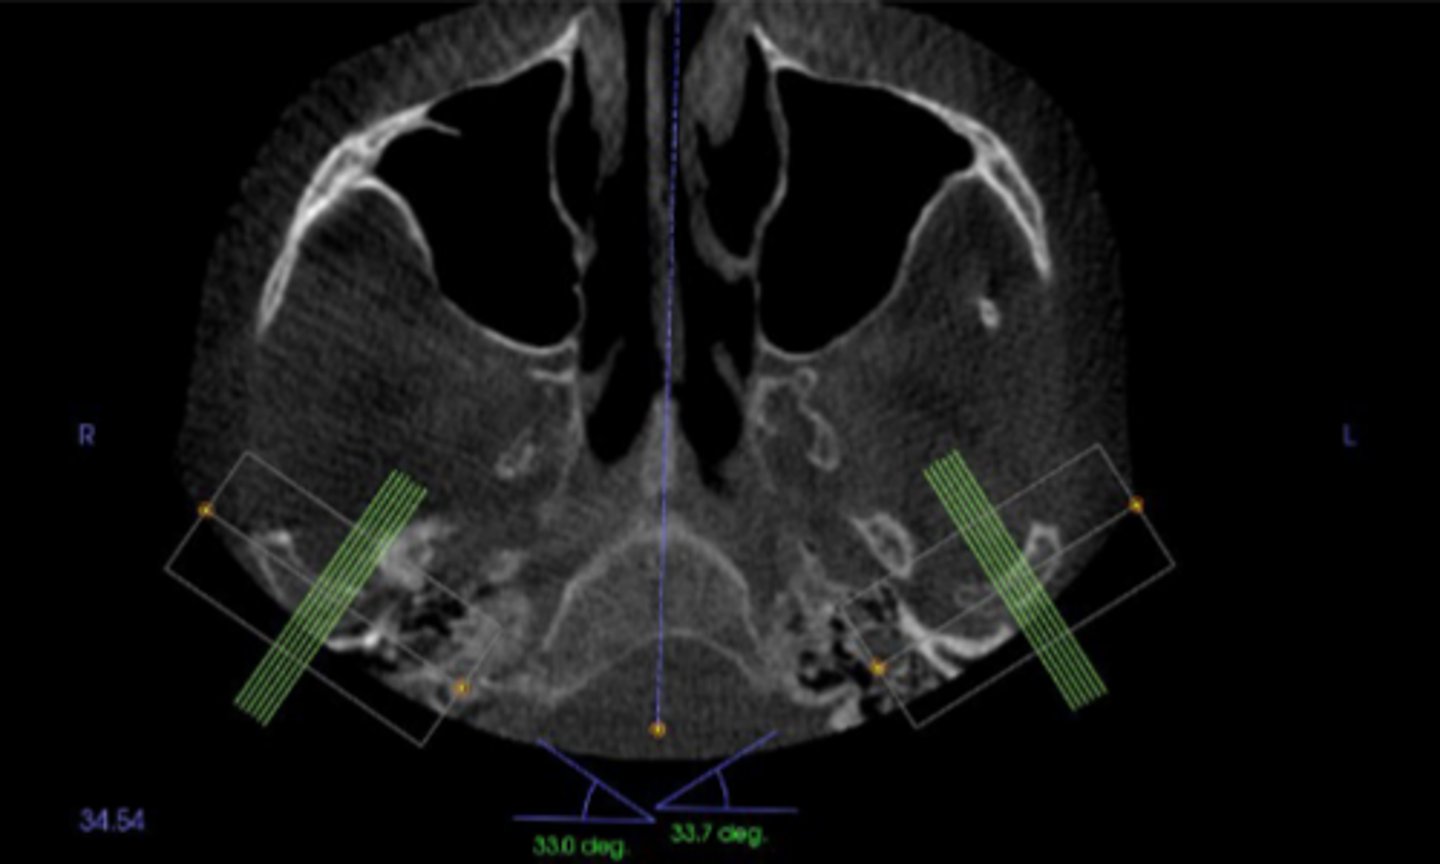

The condylar neck is angled about 15-33° with a sagittal view so that the medial pole of the condyle is located ____________ to the lateral pole.

(1)Posterior condylar positions may suggest anterior disc displacement.(2)Anterior condylar position may suggest destruction of the articular eminence, such as juvenile idiopathic arthritis. (3) Inferior condylar position may suggest fluid accumulation within the joint. (4) Superior condylar position may suggest loss, displacement, or perforation of the disc or attachments.

Match the abnormal eccentric position with the suggested pathology.

1. Posterior condylar positions may suggest

2. Anterior condylar position may suggest

3. Inferior condylar position may suggest

4. Superior condylar position may suggest

a. Destruction of the articular eminence, such as juvenile idiopathic arthritis

b. Anterior disc displacement

c. loss, displacement, or perforation of the disc or attachments.

d. Fluid or blood accumulation within the joint

The images are showing the condyle from lateral to medial, and although A looks to be posteriorly positioned both B and C look centered, so it is likely centered.

Joint positions can vary from lateral to medial pole as seen in the radiograph so to determine if the condyle is eccentrically located or centered just see where the condyle is sitting most of the time. Would the example be eccentrically located or centered?